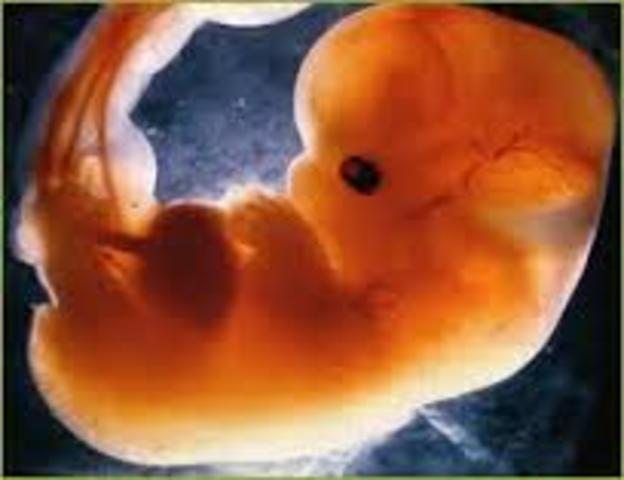

• 8ª semana

8ª semana

El embrión mide aproximadamente 3 cm. La cara adquiere un aspecto humano. Se pueden ver ojos, orejas y nariz. Los párpados cubren los ojos y los dedos están bien formados.